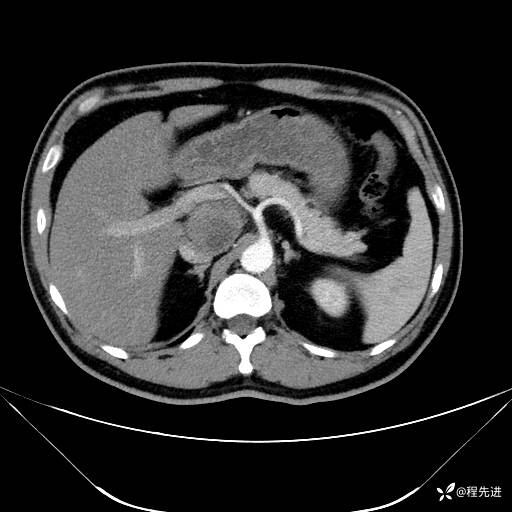

【腹盆】特别精彩病例|发现腹膜后肿物1月余

主诉:发现腹膜后肿物1月余

现病史:患者1月余前查体,行超声检查提示:后腹膜囊实性肿块;慢性胆囊炎伴胆囊内结石;无腹痛腹胀,不伴腹泻发热等;偶感腰背部酸痛。

CT平扫+增强: